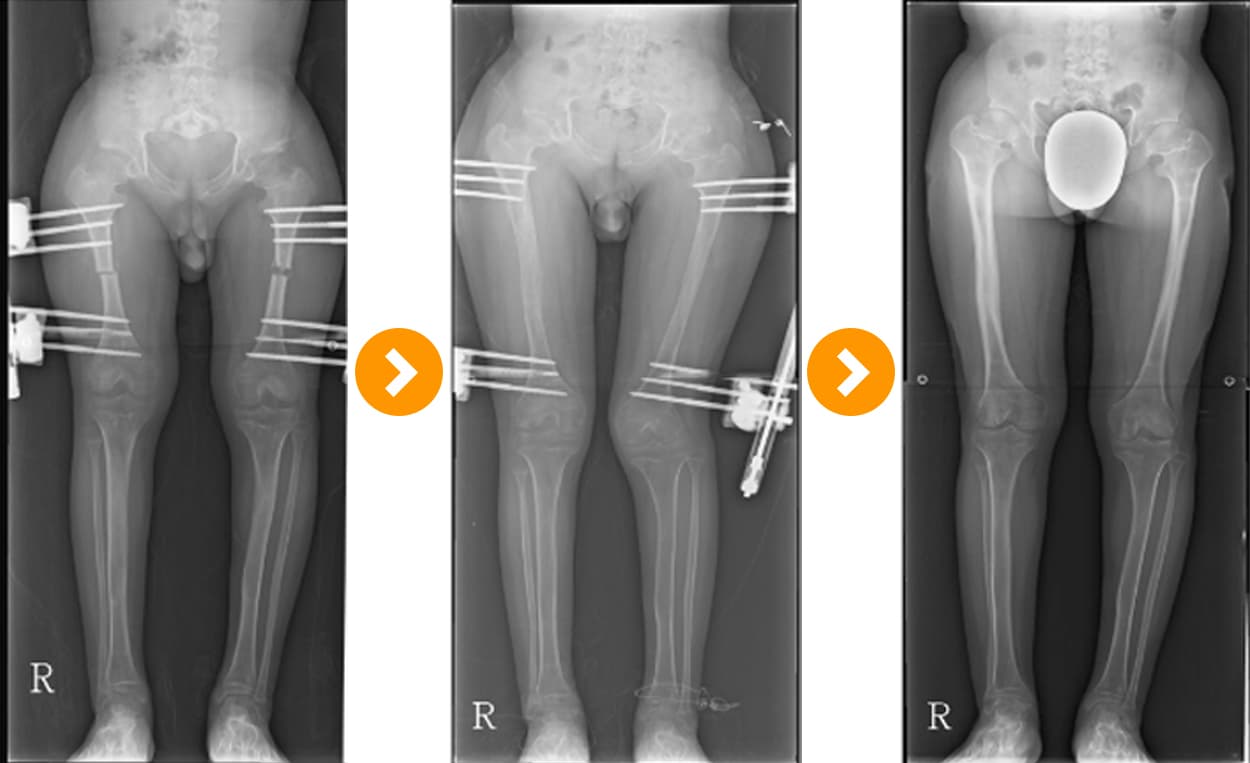

Achondroplasia: Bow Leg Correction and Bone Lengthening 10 cm